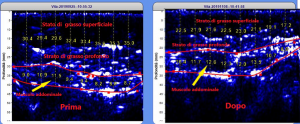

La misurazione è diretta e non derivata, per cui lo strumento fa una fotografia dello stato attuale del tessuto adiposo superficiale/profondo e del muscolo.

Il risultato che si ottiene, è un’immagine che mette in evidenza i confini tra i diversi tessuti, consentendone la misurazione e garantendo una perfetta valutazione. I dati così ottenuti sono accurati e precisi.